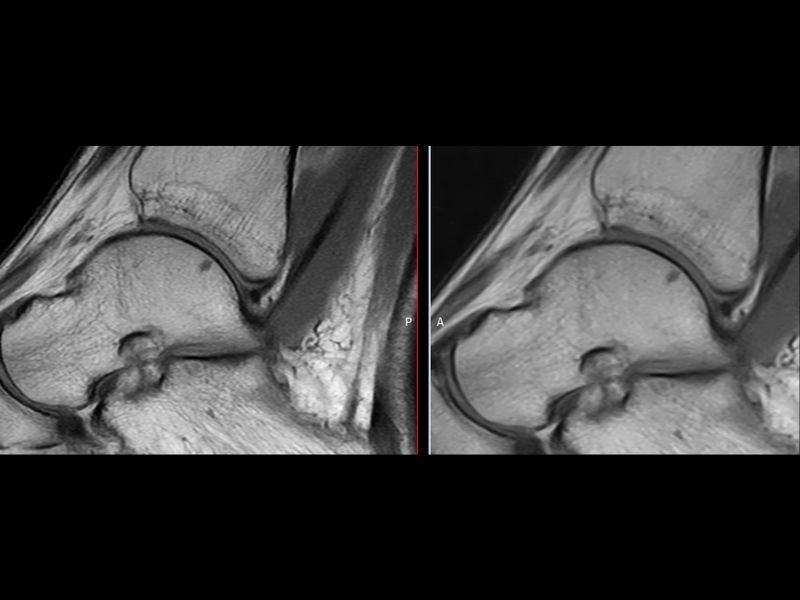

Esaote introduces Artificial Intelligence into its MRI systems as a fully integrated and customized solution. The new technological platform, e‑SPADES, consisting of advanced HW and sophisticated SW algorithms such as HyperClarity delivers unparalleled image quality.

Step into a new era for Esaote systems with HyperClarity, powered by SwiftMR™, a trademark of AIRS Medical Inc. This advanced integrated feature significantly enhances image quality by improving resolution, reducing noise, and providing physicians with a powerful tool for more consistent clinical outcomes.

Dr. Francesco Arrigoni Radiologist, U.O.S.D Dea Del P.O. San Salvatore, L’aquila, Italy, remarked during the last ECR: “e‑SPADES technology includes different software based on deep learning technology. These tools work at different points along the workflow for the production of the imaging. HyperClarity makes images clearer and of higher quality, allowing for immediately recorded diagnoses avoiding repetition of examination”.

Clinical Images